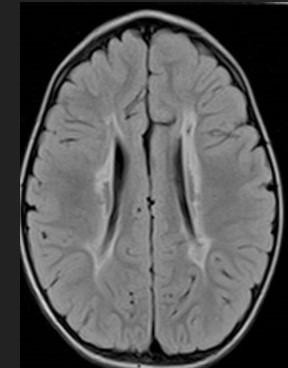

Konuşma, soyut kavramlar, matematik, okuma-yazma, sosyal ilişkiler, duygular, iç görü beynin bilişsel (kognitif) işlevleridir. Yaş ve eğitimle değişebilen bir bilişsel kapasite vardır. Bu bilgilerin etkin kullanılması ve ilişkilendirilmesi ise zeka veya zihinsel beceridir . Yaşa göre beklenen kapasitenin veya ilişkilendirmenin olmaması zihinsel yetersizlik olarak tanımlanır. "Zeka geriliği", teknik olarak aynı anlamdaysa da ifadenin negatif duygusal yükü fazladır. "Mental retardasyon" ise medikal ifadedir.

Çocuğun gelişiminde zihinsel yetersizlik hem bilişsel kazanımların yaşa göre geri kalması hem de bunların kullanımında hatalar şeklinde ortaya çıkar. İlk olarak bilişsel kapasitenin yaşın gerisinde kalması bir belirtidir: konuşmayı öğrenememek, sayı ve renk kavramlarının gelişmemesi gibi.

Beyin hasarı olan çocuklarda bebeklik döneminde önce hareket gerilikleri görülür ve ele alınır. Zihinsel beceriler daha sonra fark edilir. Konuşma insan beynine has üst düzey bir bilişsel beceridir ve zihinsel kapasitenin iyi bir göstergesidir. Bazen hareket gecikmeleri atlatılsa da zihinsel yetersizlik kalabilir.